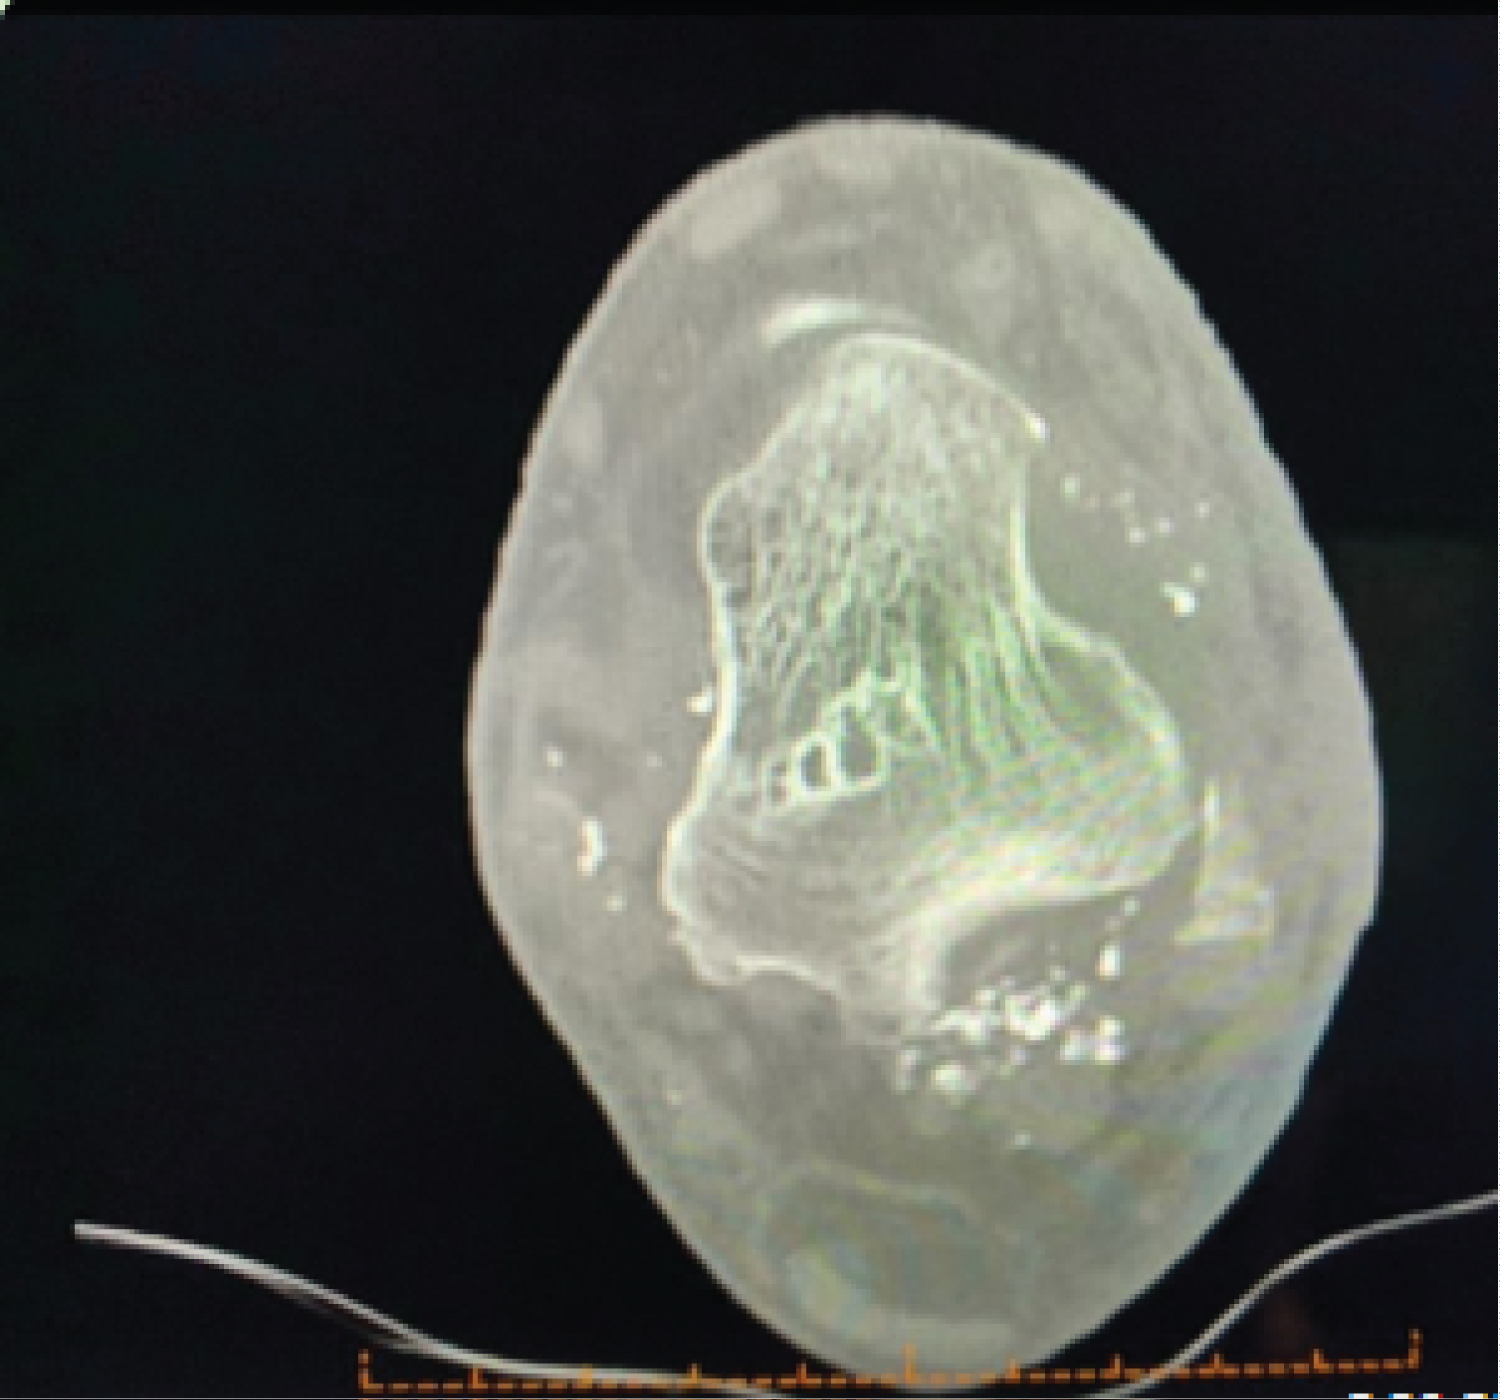

An MRI was performed after the operation to look for evidence of malignancy. A T2 hyperdense lobular lesion was found in the ankle and subtalar joints and this appearance suggested the diagnosis of SC with no other notable features pointing towards to a malignancy. The MRI also showed multiple deposits remaining in the ankle joint.

Patient was pain free post-surgery supporting a diagnosis of lateral impingement caused by the tumour mass. Bone tumour units in Royal Prince Alfred and New York Bone Tumour reviewed the histology as seen in Figure 2 and suggested complete excision of all SC deposits. Further resection was then performed and no malignant transformation identified (Figure 3).

Figure 3: MRI performed post first surgery showing multiple deposits around the ankle joint. View Figure 3